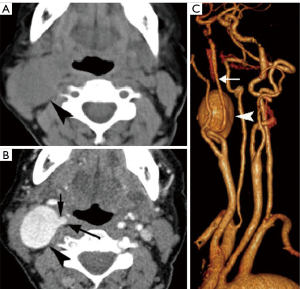

Aneurysm, pseudo-aneurysm, and arteriovenous fistula (AVF)

Vascular masses originating from the carotid space are rare, varying from aneurysm, pseudo-aneurysm, to carotid dissection, atherosclerosis, thrombus in the ICA or IJV, and fibromuscular dysplasia, which are identifiable on both MRI/magnetic resonance angiography (MRA) and CT/CTA (35-37). ICA aneurysm, usually arising from atherosclerotic ICA, is identified by their intimate relationship and synchronous enhancement with the ICA on CT or MR imaging (Figure 14). Pseudoaneurysms are often secondary to neck trauma and result from partial to complete disruption of the vascular wall, ultimately leading to hemorrhage contained by the adventitia of the vessel wall or perivascular soft tissues (Figure 15) (36). Neck AVF is usually a result of trauma which causes partial transaction of an adjacent artery and vein. AVF tends to be more clinically apparent. Contrast-enhanced CT may show direct communication between and synchronous of the artery and vein (Figure 16).